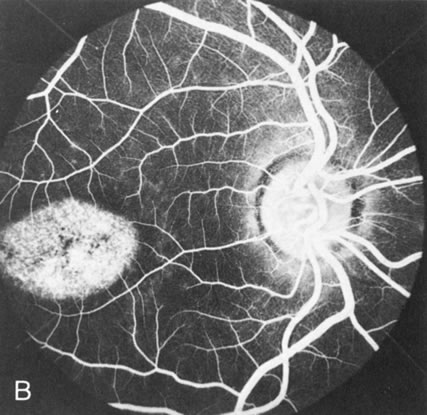

In retinitis pigmentosa (RP), the pigment abnormalities of atrophy, migration, and clumping are made apparent by transmitted hyperfluorescence and blocked hypofluorescence (Fig. 1A). Patients who have very minimal pigmentary alterations (pauci pigmentary RP) or no pigment abnormalities (RP sine pigmento) may show the abnormalities on fluorescien angiography (FA). It is uncommon to see choriocapillaris atrophy except in the late stages. This finding corresponds to the histopathology, which shows that the earliest abnormalities are in the photoreceptors and that the choroid is normal.1

Fig. 1. Retinitis pigmentosa. A. A typical area of bone spicule pigmentation. B. Diffuse dye leakage is apparent throughout the posterior pole. C. The early angiogram shows dilated and irregular retinal radial peripapillary capillaries and perifoveal retinal capillaries. D. Leakage from these vessels are evident in the late angiogram.

Dye leakage in RP may occur from the retinal vessels or at the level of the retinal pigment epithelium (Fig. 1B).2–4 The leakage may be seen in the macula and posterior pole, along the vascular arcades in the distribution of the radial peripapillary capillaries, and in the periphery (where an exudative vasculopathy resembling Coats' disease is suggested).

Of more clinical importance is the role of FA in the diagnosis and treatment of cystoid macular edema (CME) (Fig. 1C and D). Stereoscopic FA indicates that the leakage, which may be diffuse or have the typical petaloid stellate appearance of CME, can come from the perifoveal retinal capillaries, from the choroid through the RPE, or from a combination of both sources.4 With the recent suggestion that CME in RP may be successfully treated with acetazolamide,5, 6 FA is thus important to document the diagnosis of CME, establish the origin(s) of leakage, and follow patients during and after therapy.